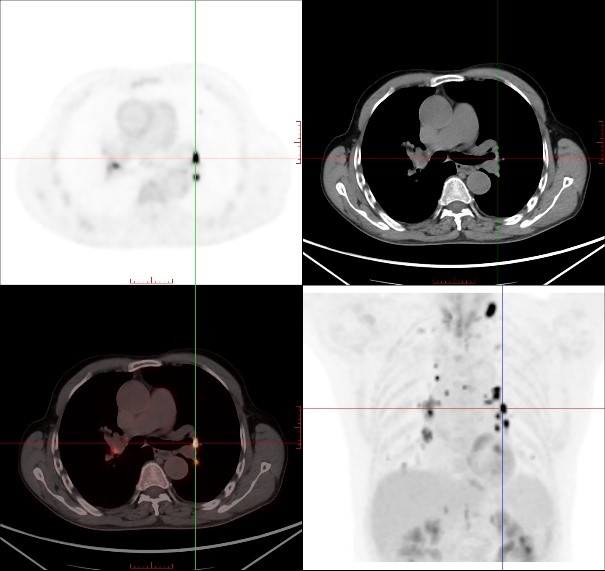

因此,临床医生给患者进行了传统的颈胸部增强CT检查以了解术后颈部情况,并试图寻找可能存在的原发病灶,但令人遗憾的是,增强CT并没有发现原发灶及转移相关证据。于是,医生决定给患者做一个全身PET/CT检查。

对于贺老伯来讲,超声及颈胸部增强CT检查均未能发现颈部、纵隔及肺门异常淋巴结,而PET/CT准确地找到这些异常淋巴结,就像多盏灯将这些隐藏的可疑淋巴结点亮一样,让可疑病灶无处遁形,为临床确定精准治疗方案提供帮助。